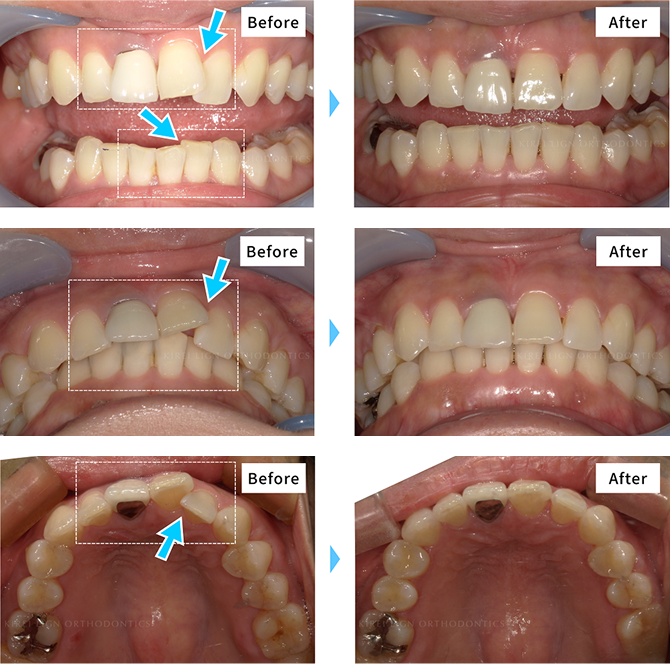

矯正治療の症例

キレイラインを4回実施

- [ 治療期間 ] 約4ヶ月半

- [ 治療費用 ] 160,000円

(税込176,000円)

- [再診料] (5回 15,000円 (税込16,500円)

- [追加治療] 上顎左右2番矮小歯の補綴

※効果には個人差があります。

※補綴・治療の費用は各提携クリニックによって異なります。